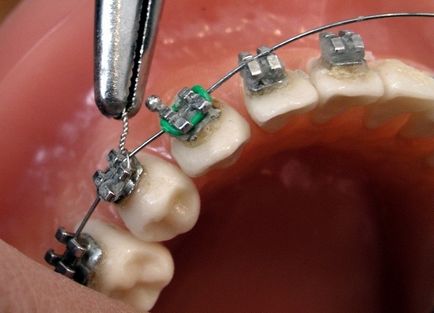

Скоба система - механизъм, състоящ се от пръстен с ключалки, скоби, лигатури, арка и еластична отката.

Монтаж такъв дизайн включва невъзможността да се изваждането му преди края на лечението, тъй като настройката се извършва със специална смес за лепене. След свързване, всички елементи са свързани чрез дъги, които, от своя страна, се изравни с лигатури. Фиксиращи пръстени и букални ключалки се извършва на 6 и 7 зъби. Освен това, някои скоби могат да имат метал кука, предназначени за определяне на еластичния натиск понякога е необходимо в процеса на лечение. Така, етапите на монтиране скоби включват множество нюанси.

При закрепване болка система е напълно отсъства.

Това се дължи на факта, че основните елементи на скобите са поставени до зъби със специално лепило, всички следващи детайлите, прикачени към тях вече. Единственото нещо, което може да се очаква при пациент по време на инсталирането на устройството - малко неудобно, когато превръзка дъга канали вече залепени към зъбите на елементи, причинени от необходимата механична налягане. Като цяло, на инсталационната процедура е безболезнена.